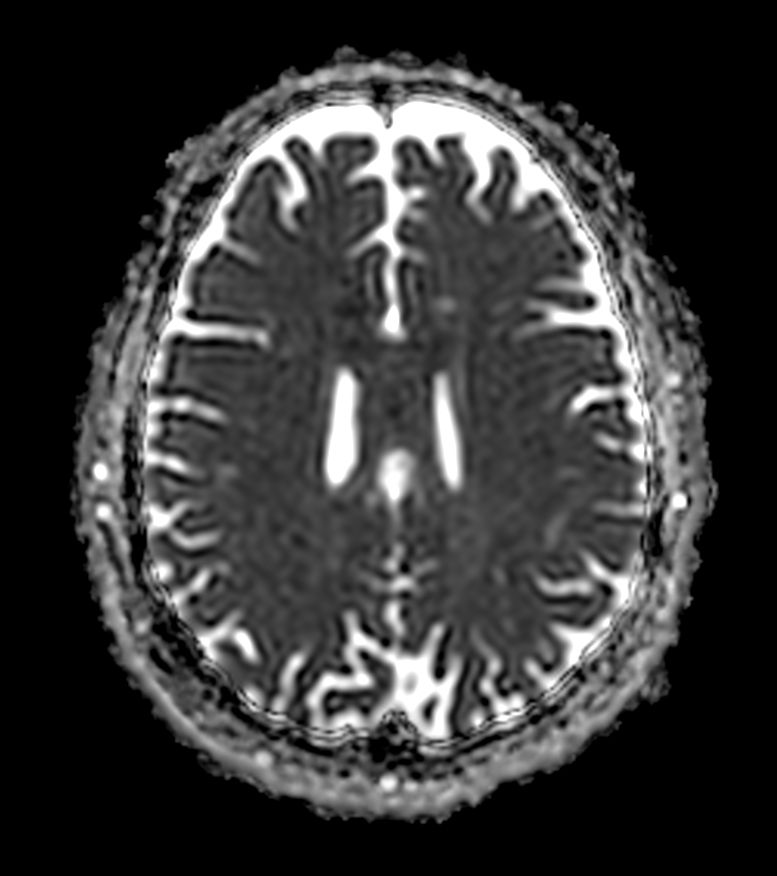

Diffusion b1000

-

Diffusion b1000 (ADC)